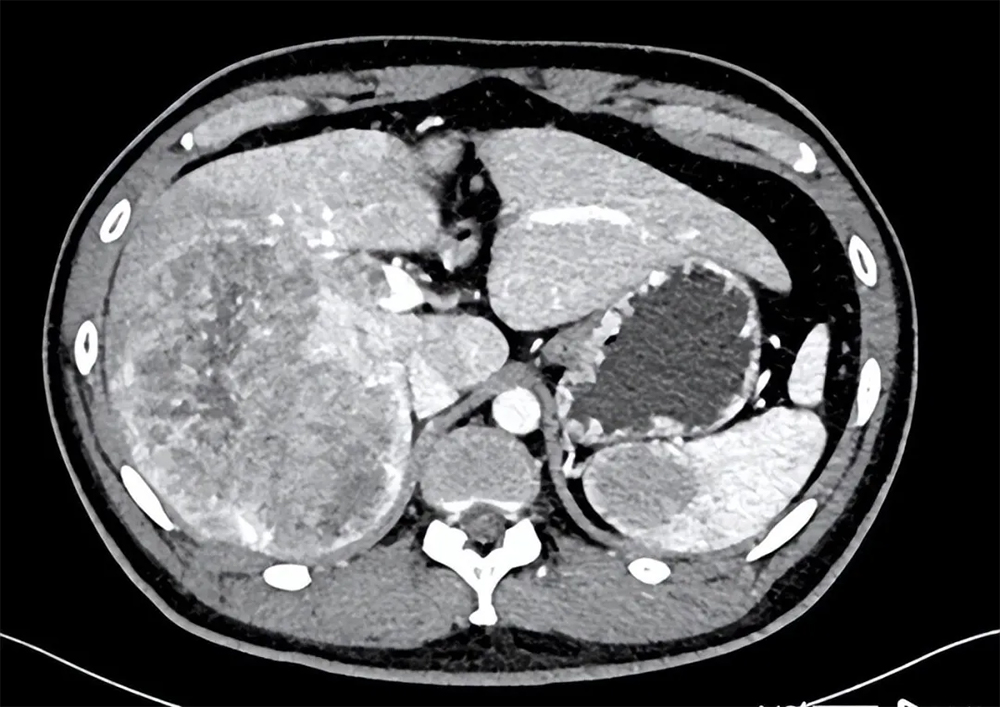

患者李先生21年被确诊肝癌晚期,由于肿瘤较大,正常肝脏已经不足30%,如果切除,剩余肝功能无法支撑人体的正常需求,加上肿瘤已经侵犯血管,形成癌栓,并且逐渐向脾脏出现转移,经医生评估后认为已经无法通过手术切除肿瘤。

在经过治疗后:复查肿瘤体明显萎缩,肿瘤相关生物指标也在不断下降。到2022年4月份复查CT,肿瘤总体积已经缩小了一半多,剩余肝脏体积也明显增加。